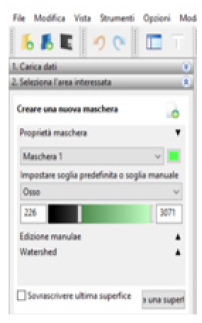

Following the import, the software allows to visualize the biological structure of interest in the three main axes of the human body (Figure 8)[10]. The next step is to segment the image using a colored mask. The mask is nothing but gray threshold level comparable to a certain tissue density. By setting the density range, the software highlights a specific region and creates its three-dimensional model, eliminating the rest. There is the possibility of pre-defined range (for example: compact bone, spongy bone, skin, muscular tissue etc.) or it can be changed manually. After the correct identification of the mask, the 3D surface is generated using the proper command (Figure 9). In the analyzed case it was preferred to use the “ Compact bone (adult) “ because the range was more limited avoiding other possible tissue inclusion. When the mask covers the right areas, the creation of the three-dimensional surface is performed. This is displayed in the lower right window (Figure 10). Once the 3D surface is created and exported in STL format for further modifications. Generally, the mesh created by In Vesalius is coarse and not homogeneous, so it needs an optimization process.